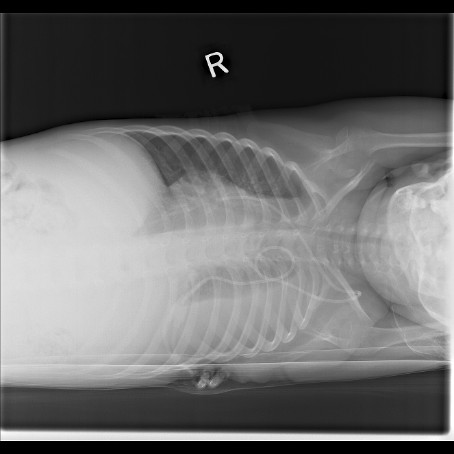

A chest X-ray with posterioanterior, lateral and left lateral decubitus views was also obtained: